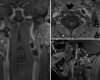

Background: Cervical schwannoma is a rare neoplasm that usually occurs like a nondolent lateral neck mass but when growing and symptomatic requires radical excision. Sodium fluorescein (SF) is a dye that is uptake by schwannomas, which makes it amenable for its use in the resection of difficult or recurrent cases.

Methods: We describe the case of a patient presenting with a recurrence of a vagus nerve schwannoma in the cervical region and the step-by-step technique for its complete microsurgical exeresis helped by the use of SF dye.

Results: We achieved a complete microsurgical exeresis, despite the presence of exuberant perilesional fibrosis, by exploiting the ability of SF to stain the schwannoma and nearby tissues. That happens due to altered vascular permeability, allowing us to better differentiate the lesion boundaries and reactive scar tissue under microscope visualization (YELLOW 560 nm filter).

Conclusion: Recurrent cervical schwannoma might represent a surgical challenge due to its relation to the nerve, main cervical vessels, and the scar tissue encompassing the lesion. Although SF can cross both blood-brain and blood-tumor barriers, the impregnation of neoplastic tissue is still greater than that of nonneoplastic peripheric tissues. Such behavior may facilitate a safer removal of this kind of lesion while respecting contiguous anatomical structures.